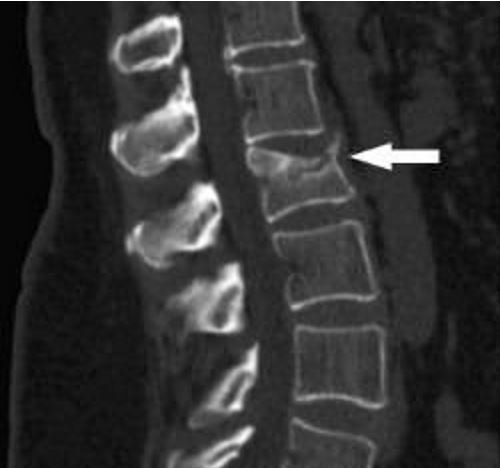

Симптоматика зависит от тяжести травмы: повреждён спинной мозг или нет. Для диагностирования используется рентген, компьютерная томография, МРТ и другие методы.

- Компрессионный тип. Возникает вследствие падений с приземлением на спину, таз или ноги.

- Сгибательные и разгибательные травмы. Их причина: падение на спину, резкое разгибание какого-либо отдела позвоночника при ДТП.

- Ротационная травма. Возникает из-за резкого движения позвоночного столба относительно своей оси (вращением). Нередко это вызвано сильным ударом по корпусу.

Также переломы позвонков и связанных с ними структур можно разделить на стабильные и нестабильные. Стабильное повреждение происходит без грубого нарушения структуры костей и смещений, а для нестабильного характерно смещение костей, травмы с вывихом и разрывом связочного аппарата.